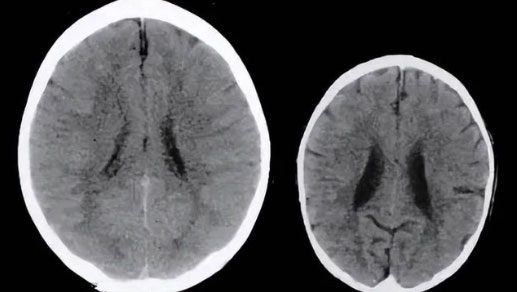

Theo Sohu, các nhà khoa học đã tiến hành quét hình ảnh bên trong não của hai đứa trẻ 3 tuổi có cùng giới tính và điều kiện gia đình. Tuy nhiên, điểm khác biệt giữa hai đứa trẻ là một em thường xuyên bị phụ huynh la mắng, trong khi em còn lại thì không.

Sau đó, kết quả nghiên cứu chỉ ra não bộ của trẻ hay bị la mắng nhỏ hơn rất nhiều so với bạn của mình. Điều này chứng tỏ hai đứa trẻ này đã có sự phát triển trí não chênh lệch dù cho chúng có cùng xuất phát điểm. Nguyên nhân của hiện tượng này là khi con cái bị cha mẹ la mắng và phớt lờ suy nghĩ, não bộ của chúng sẽ ngừng phát triển và thậm chí co lại.

Kết quả nghiên cứu cho thấy trẻ hay bị phụ huynh la mắng (bên phải) có não bộ nhỏ hơn rất nhiều so với bạn đồng trang lứa.